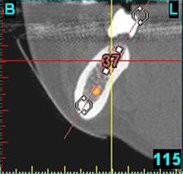

In komplexen Fällen, z. B. der Implantatversorgung eines kompletten Kiefers, oder bei schwierigen Knochensituationen bietet die 3-dimensionale Computerdiagnostik bzw. Planung und Durchführung erhebliche Vorteile und Sicherheit für den Patienten (siehe Bild 1 und 2).

Auf Basis einer computertomografischen (CT-) Kieferaufnahme ist eine dreidimensionale Darstellung der Knochen möglich. Der Zahnarzt kann dann am Computerbildschirm die Knochenqualität (z. B. Knochendichte) beurteilen und die optimale Position der Implantate im Vorfeld planen. Durch Verwendung spezieller Röntgenschablonen lässt sich auch die erwünschte Zahnstellung in die Planung einbeziehen. Die Simulation der OP erlaubt, das zu erwartende Ergebnis mit größtmöglicher Sicherheit vorherzusagen und dem Patienten am Bildschirm zu veranschaulichen.

(siehe Bild 3 und 4).